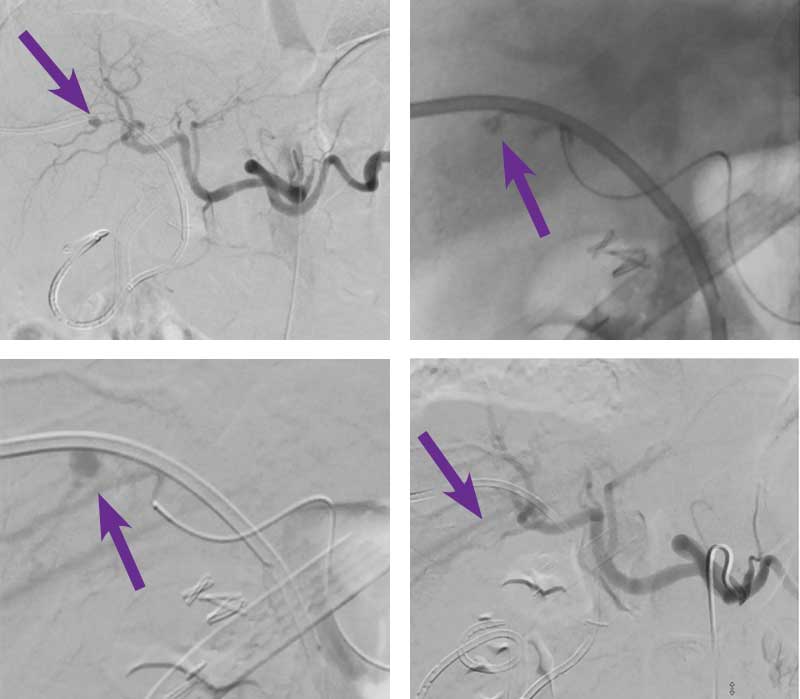

Right hepatic artery pseudoaneurysm embolization

Courtesy of Dr. Abhishek Kumar I Rutgers New Jersey Medical School

68-year-old man s/p open cholecystectomy complicated by bile duct injury and bile leak presented for percutaneous transhepatic biliary drainage. A week following right internal/external biliary drain placement, the patient returned a week later with blood in the drainage bag.

Intervention used

Right femoral arterial access was obtained and a 5 F sheath was placed. A 5 F Sos catheter was used to select the celiac artery and an angiogram was performed. Angiography demonstrated a pseudoaneurysm of a right hepatic artery branch adjacent to the biliary drain (arrow). A 2.4 F microcatheter and 0.014” wire were then used to catheterize the vessel supplying the pseudoaneurysm. The vessel was embolized with 0.2 cc of Obsidio Embolic using a slow injection rate to allow the embolic to flow distally into the pseudoaneurysm. Post-imaging depicts the Obsidio Embolic cast. A completion celiac angiogram demonstrated complete embolization of the hepatic artery pseudoaneurysm.

The patient was discharged home 4 hours following the procedure with no recurrence of bleeding.

Scan images from Obsidio right hepatic artery pseudoaneurysm case.